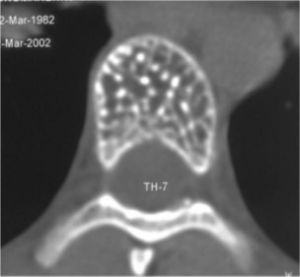

МРТ2

Рис.№ 2. КТ Th7 позвонка. Поражение гемангиомой всего тела Th7 позвонка.